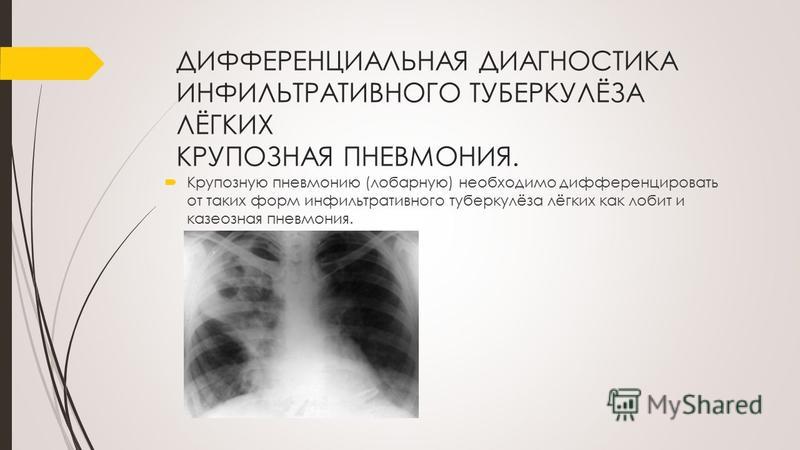

Дифференциальная диагностика заболеваний плевры